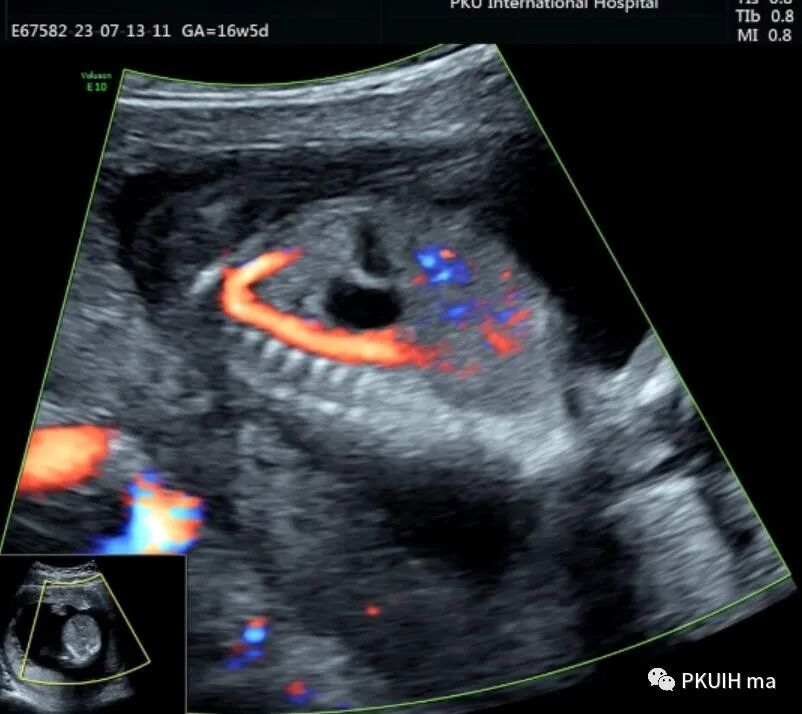

孕妇16周+5天常规超声检查发现腹部一囊性包块,如下图

胎儿中腹部见一囊性包块,大小约1.2x1.0x0.8cm,边界清,形态规则,内透声好。囊肿位于脊柱前方、胆囊后方、门静脉窦旁,与后肾接近

观察囊肿与肾、胃泡、膀胱均无相关。

仔细观察囊肿壁好像不完整,周边见微小管道回声与囊肿相通

CDFI:囊肿内未见明显血流信号。

由于囊肿位于胆囊后方、肝下方、门静脉窦旁,随考虑为胆总管囊肿

本病可于中孕及晚孕期被发现,其超声特征为肝门区囊性包块,形状呈圆形或椭圆形,位于门静脉右前方,可对门脉造成压迫。如果显示囊性包块与胆囊相通,则有助于诊断,彩超一般内部无血流信号。